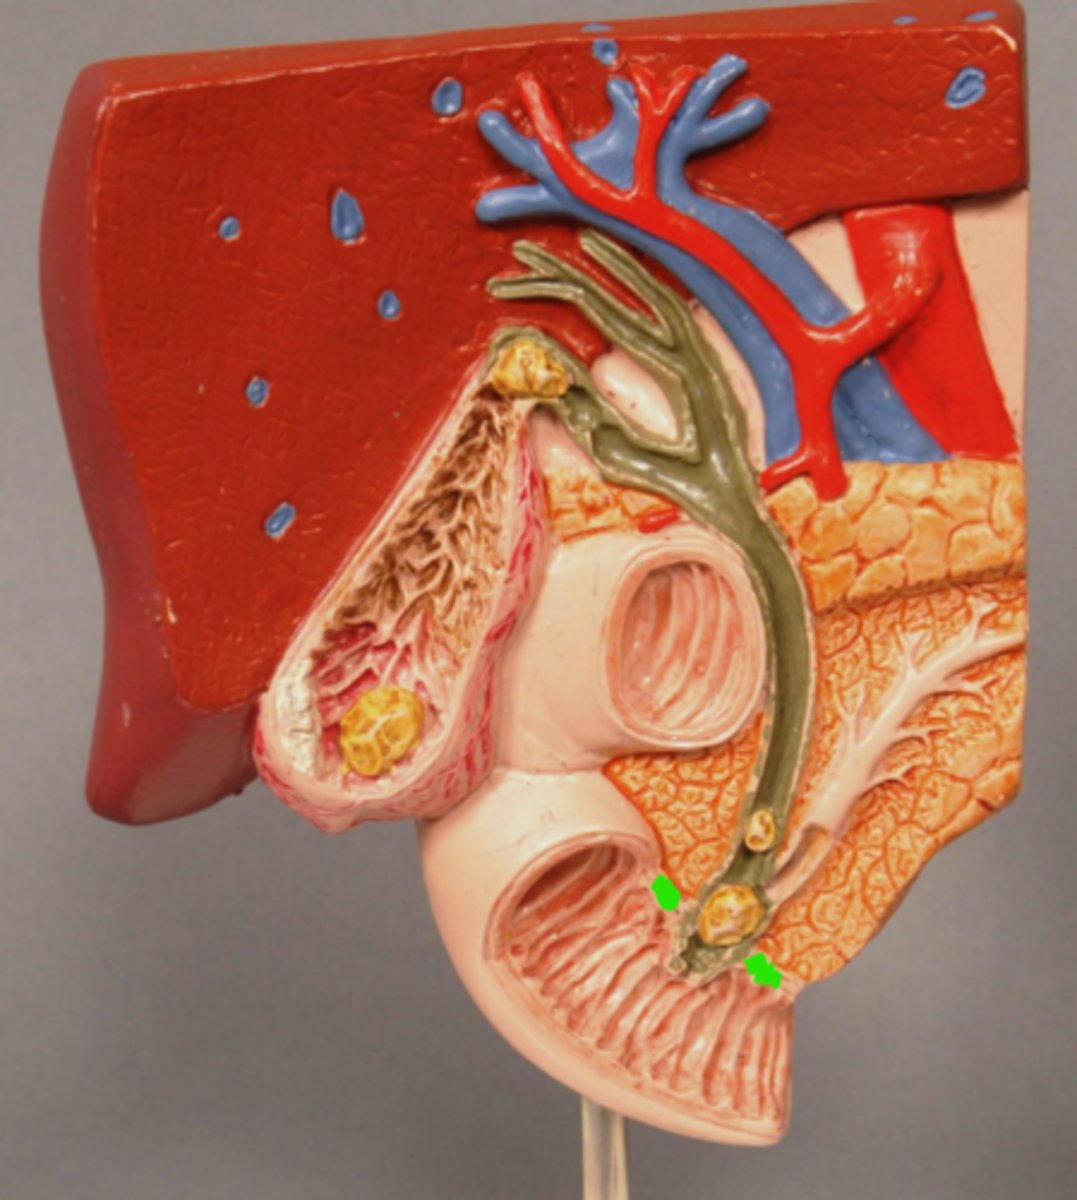

Sphincter of Oddi

Gallstone in Ampulla of Vater